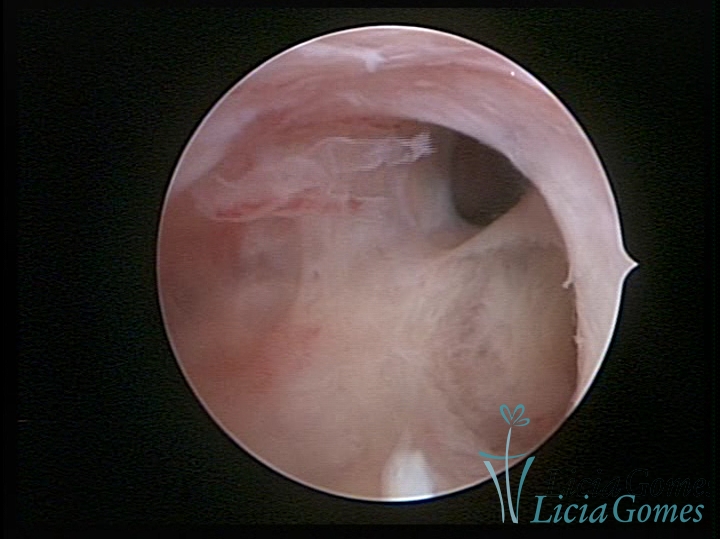

Sinéquia TIPO FIBROSA

As Sinéquia uterinas são cicatrizes (aderências) entre as superfícies das paredes uterinas, que podem ocorrer após manipulação cirúrgica, ou curetagem uterina, ou após um processo inflamatório na cavidade uterina (endometrite), podendo levar a alterações menstruais, infertilidade, e complicações obstétricas, como abortamento, parto prematuro.